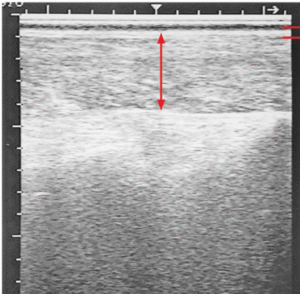

در این دوره بدن گاو شیری دچار تعادل منفی انرژی شده و برای تأمین انرژی موردنیاز بافت پستانی و بافت ماهیچهای نیازمند انتقال گسترده چربیها از بافت چربی به کبد است. کبد بهمنظور خارج کردن NEFA به شکل VLDL، وابسته به حضور فسفاتیدیل کولین است. در صورت عدم کافی بودن کولین بخش زیادی از چربیها در کبد تجمع مییابد. از اینرو در وهله اول بهبود ماده خشک مصرفی و سپس استفاده از کولین پوششدار و الباقی ملزومات در دوره انتقال و اوایل شیردهی در گاوهای شیری بسیار حائز اهمیت است. هر 0.1 درصد کاهش در میانگین ماده خشک مصرفی به ازای درصد وزن بدن (DMI%BW) در 3 روز قبل از زایمان بر سلامتی گاوها تأثیر میگذارد:

- در طی دوران انتقال، مکمل کولین غلظت NEFA پلاسما را تغییر میدهد. این امر خروج و انتقال چربی کبد را افزایش میدهد و منجر به کاهش غلظت چربی کبد و کاهش خطر ابتلا به کبد چرب میشود. در صورت استفاده از کولین پوششدار قبل و بعد از زایمان، خطر ابتلا به کتوز بالینی و تحت بالینی و عوارض کلی کاهش مییابد.